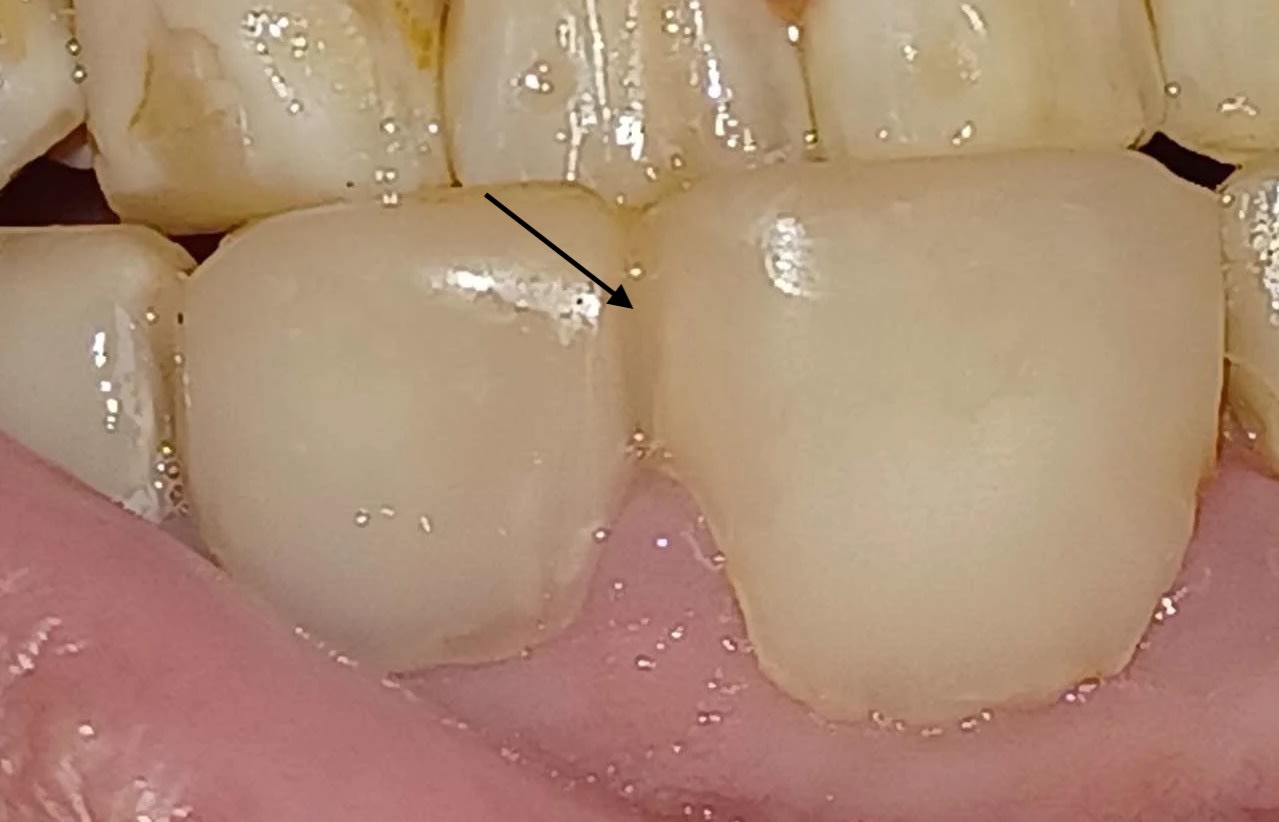

Mon collégue et moi ne parvenons pas à déterminer si ce sont des composites débordants ou des facettes.

Connaissez-vous une technique fiable pour déterminer si c'est l'un ou l'autre ?

Y’a pas de doutes c’est clairement des compos.

Par contre que les compos aient été réalisés à la 6 4 2 , cela ne fait guère de doute.

Suis du même avis. Les compos ont très probablement été réalisés pour masquer une hypoplasie de l’émail.

Les dents sont parfois même solidarisées au compo.